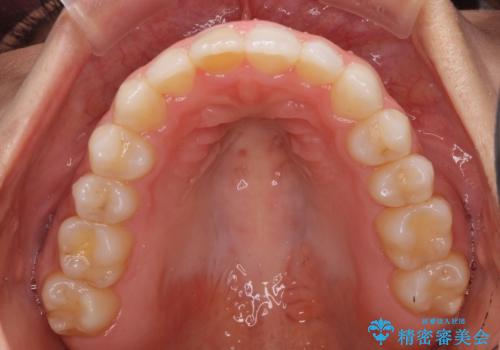

- 上下の前歯のデコボコと奥歯の反対咬合を気にして来院された患者様です。

インビザラインを用い、上下顎ともにIPR(歯と歯の間を削る)により叢生を改善することとしました。

奥歯の反対咬合は、骨格に由来するものであるため、改善できるところまで改善していくこととしました。